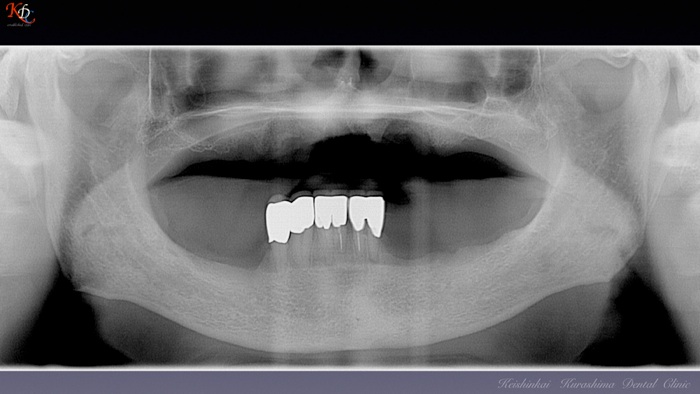

咬合再建・咬合回復shapeimage_22_link_0

症例に応じた治療手法の選択と咀嚼機能再現の効果http://www.kura-dent.com/Treatment%20and%20effects.pdfshapeimage_23_link_0